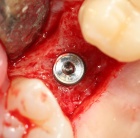

Leicht und praxisorientierte Fortbildung, um fit für das erste eigene Implantat zu werden. Halten Sie den Anschluss und bleiben konkurrenzfähig mit Ihren Kollegen.

Lernen Sie mit eindrucksvollen Full Hd Videos das operative Vorgehen wie bei einer Live OP, ohne die üblichen Wartezeiten.

Werden Sie fit für Ihren ersten eigenen Sinuslift.

Erfahren Sie, welche Fehler Sie unbewusst beim Implantieren machen können. Lernen Sie Ihr eigenes Implantat System anhand des Bohrprotokolls einschätzen und zu beurteilen. Wichtige knochenbiologische Kenntnisse.